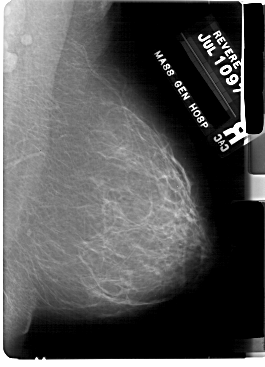

A_1756_1.LEFT_CC

LEFT_CC LINES 5491 PIXELS_PER_LINE 3781 BITS_PER_PIXEL 12 RESOLUTION 43.5 OVERLAY